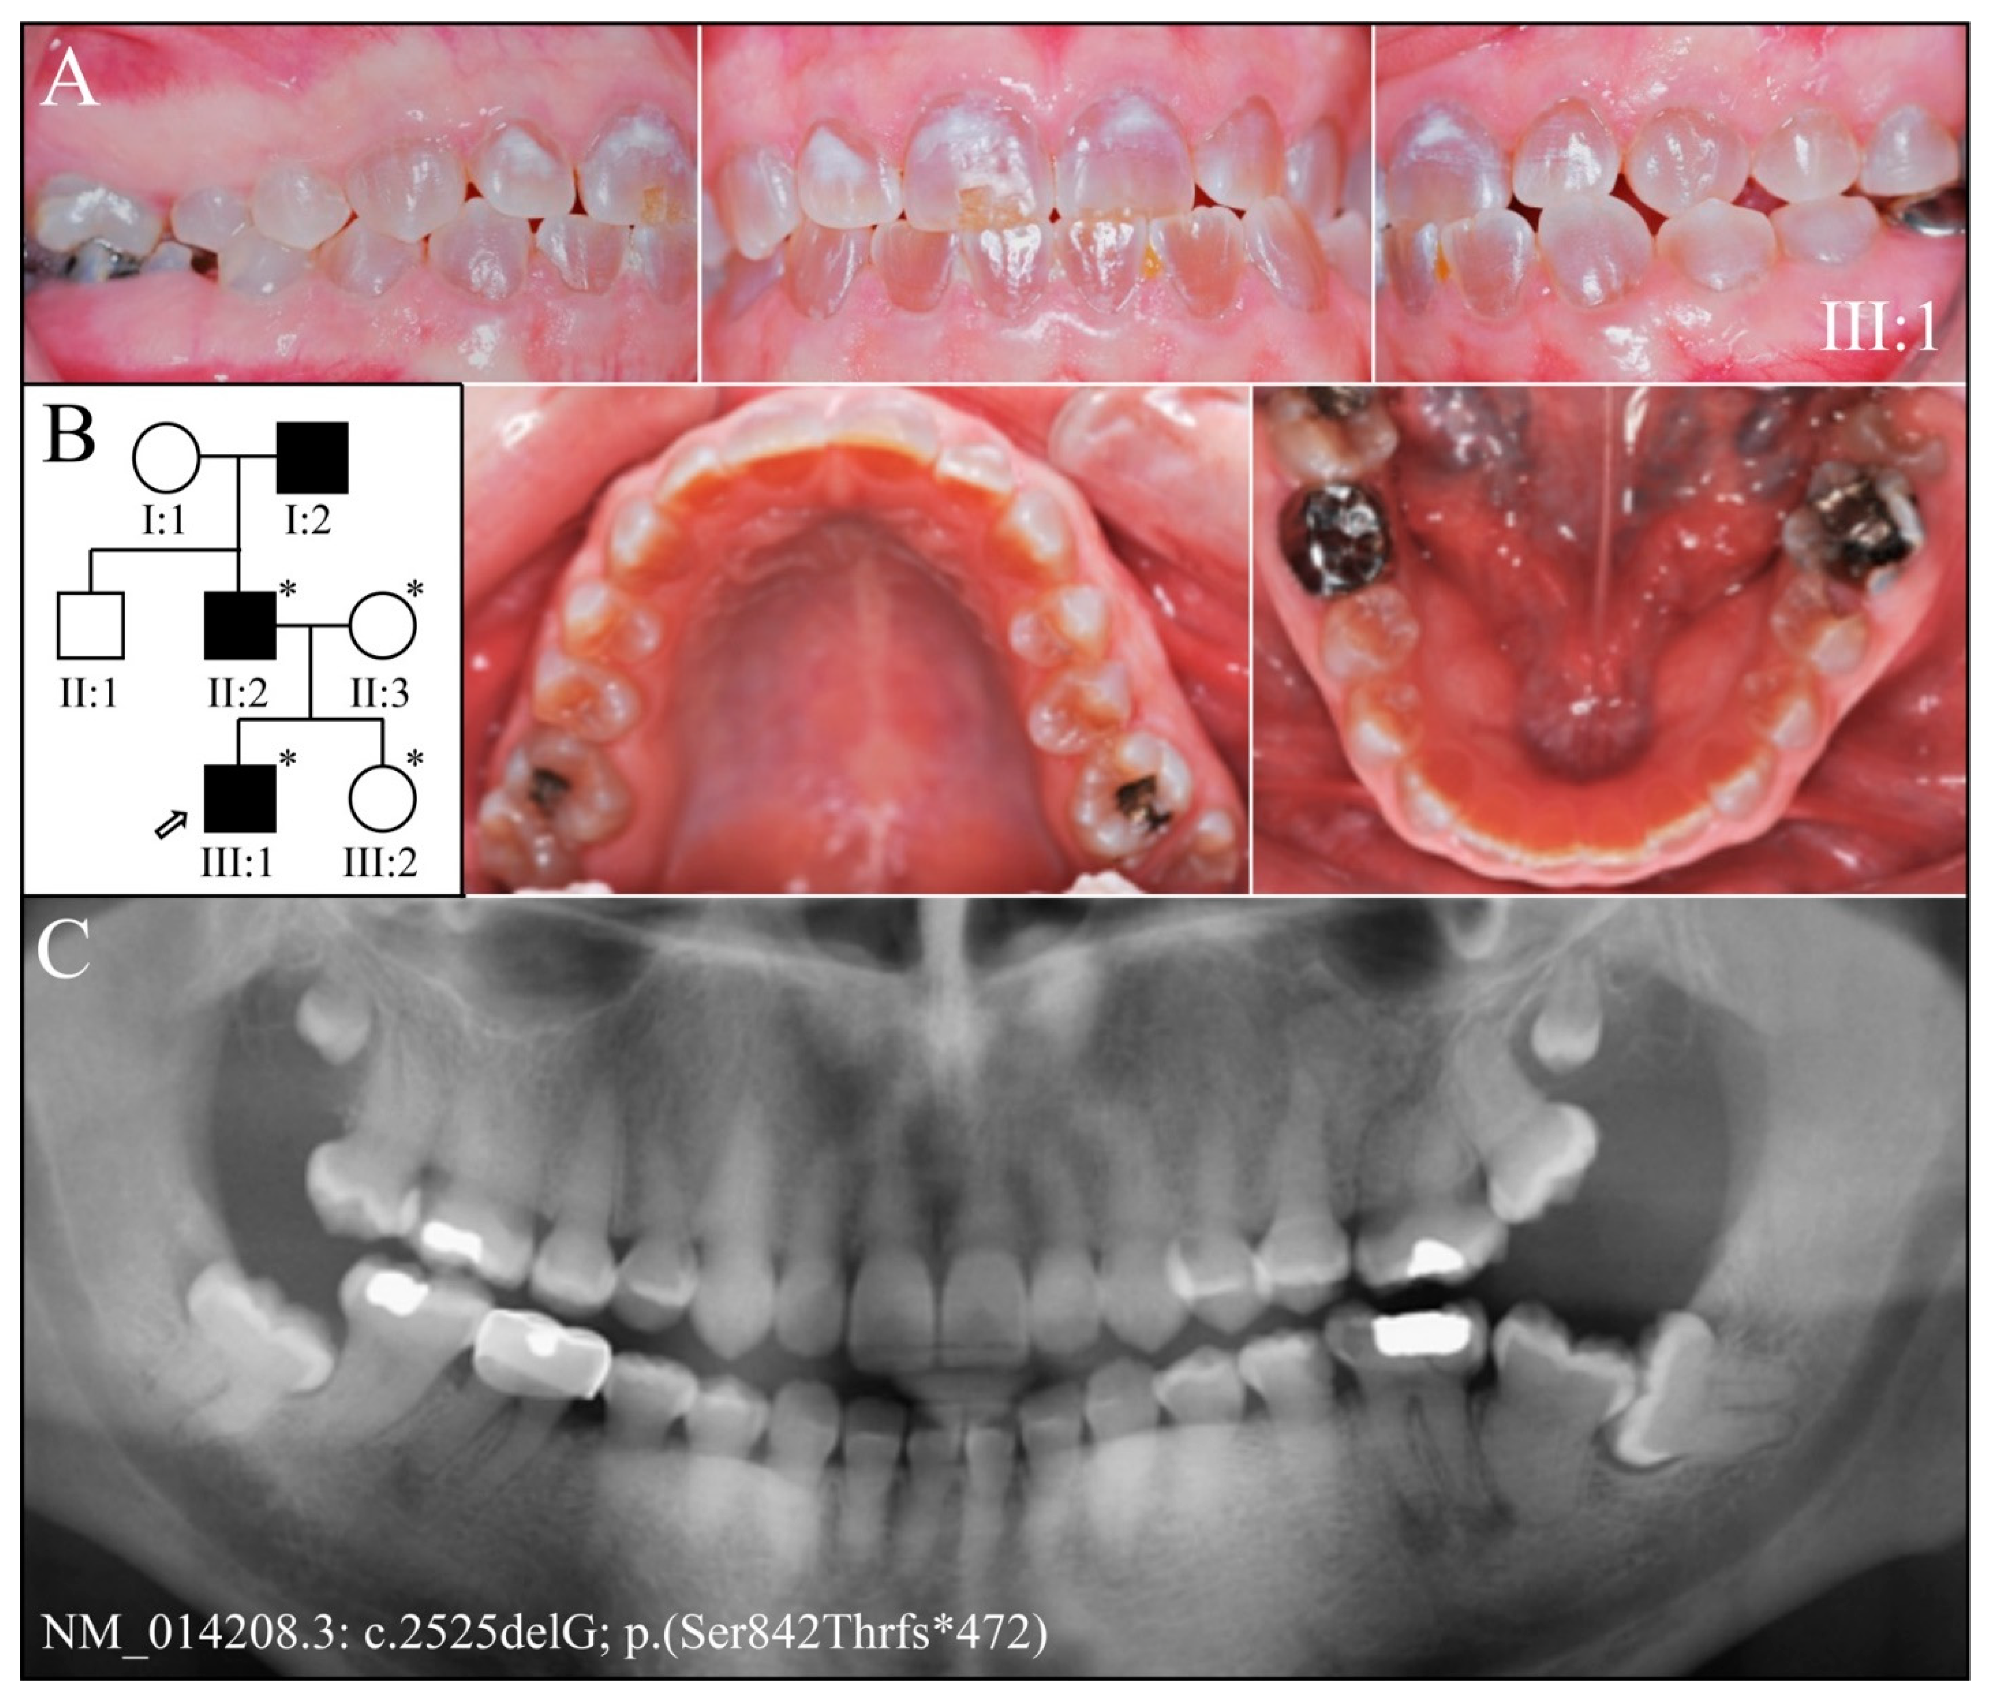

3.2. Four Families with DGI-III: 5′ DSPP Mutations

3.3. Eight Families with 3′ DSPP Mutations Causing DD-II or DGI-II